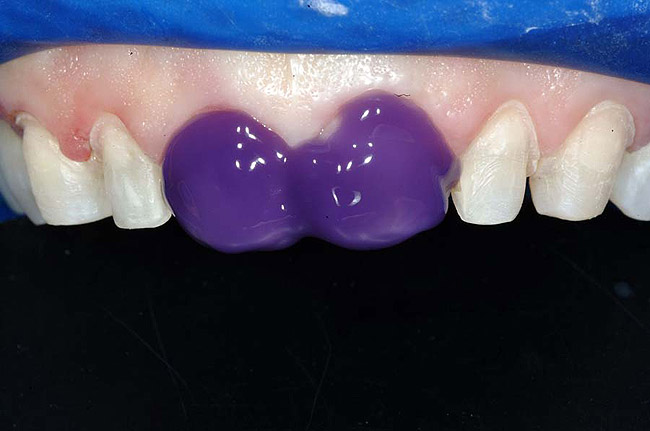

For example, before initiating the cementation process, preparations must be thoroughly cleansed (Figure 3), and adequate hemostasis and isolation should be ensured (Figure 4). Although newer generations of adhesives have been shown to be more tolerant of saliva contamination,7 proper isolation and hemostasis are still advisable because saliva and blood contamination cannegatively influence the bond strength of some bonding systems.8,9 Also,consider that resin cements are preferred for esthetic restorations, including porcelain laminate veneers.10,11 Successful use of these cements is dependent upon the incorporation of proper ceramic conditioning and tooth-surface treatment (ie, multiple-step total etch or self-etch adhesive)(Figure 8');" rem="#ip:figure5 through Figure 8">Figure 5 through Figure 8) to avoid incompatibility issues with the chosen cement and/or enhance the mechanical interlocking that occurs between the porcelain/resin-cement/tooth interfaces.10-13

Figure 4 To ensure adequate cervical access and promote hemostasis, a viscous, gingival retraction paste containing aluminum chloride (Expasyl™, Kerr Corporation) was placed in the sulci surrounding the preparations.